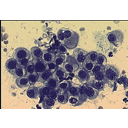

cytomodjo01.png